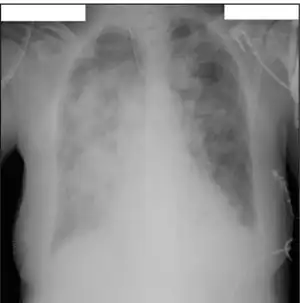

The Influenza B virus capsid is enveloped while its virion consists of an envelope, a matrix protein, a nucleoprotein complex, a nucleocapsid, and a polymerase complex. It is sometimes spherical and sometimes filamentous. Its 500 or so surface projections are made of hemagglutinin and neuraminidase.[15]